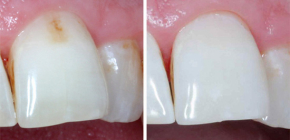

Características da cárie radicular e seu tratamento

Sabe-se que a cárie dentária se distingue por sua insidiosidade entre outros tipos conhecidos de cárie. Como a cárie dentária ocorre sob a gengiva, nem sempre é possível determinar imediatamente o problema. No entanto, complicações nesses casos podem levar a consequências realmente graves ...